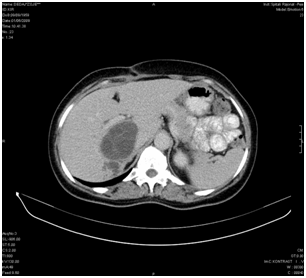

Figure 1 CT scan show a cyst situated between the portal confluence and the caval vein. Patient suffered jaundice and pain from cysto-biliary fistula.

Ten consecutive patients with liver echinococcal cysts that didn’t meet criteria for PAIR treatment (M: 4, F: 6), with a mean age of 31, 3± 14 years (range 8-54) were prospectively enrolled and operated in the Department of Surgery of Peja Hospital (Kosovo) from Feb 2006 until Apr 2010. Preoperative evaluation of the patients included blood tests (complete blood count, liver function tests and anti-echinococcus antibody testing) abdominal US and computerized tomography (CT). Five patients had single and 5 patients multiple cysts for a total number of 16 cysts. Three patients had previous surgery for hydatidosis: 1 patient had partial cystectomy 3 years before and come for recurrence, another patient with cysto biliary fistula underwent an unclear attempt to remove the cyst and cholecystectomy 3 months before (Figure 1) and another patient was previously operated for lung echinococcosis. One patient underwent PAIR 1 year before operation. According to the relationship with the main vascular and biliary structures, cysts were classified as peripheral (n= 4, 25%) or central (n= 12, 75%), when they had very close relationship with the main vessels. CT scan was considered mandatory for an adequate operative plan. RMN and ERCP were not available in the country during the study period. An intraoperative cholangiogram was obtained only in case of clinical history or laboratory tests alteration suggestive for bile duct obstruction. All patients were treated with Albendazole before surgery and in the perioperative period. Treatment was stopped immediately after surgery if during the operation the cysts were not opened. To prevent accidental spillage into the abdomen, the operative field was protected with gauzes soaked by hypertonic saline solution. Parenchymal transection was performed by clamp-crush technique. During the operation, afferent blood vessels and biliary ducts were ligated between the pericyst and the normal liver. Vessels less than 2mm in diameter were sealed using humid bipolar coagulation (Figure 2). No other devices were available to transect the liver, or glues to treat the cut surface.